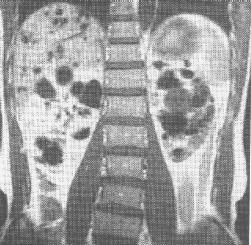

(二)發病機制主要病變是腦白質廣泛脫髓鞘,U形纖維保存,少突膠質細胞及星形膠質細胞減少。不同病例的腦白質病變可在額葉、額頂及枕葉或顳頂葉,胼胝體亦可見萎縮及多數軟化灶,病變可沿錐體束累及大腦腳和腦橋基底部。白質和基底核可見多發散在小軟化灶,腦白質直徑100~400μm的小動脈及細小動脈可見內膜纖維化、玻璃樣變、內彈力層斷裂、管徑狹窄及閉塞等。腦底部大血管無異常或輕度動脈粥樣硬化,顳動脈活檢直徑800μm的小動脈可見內膜肥厚,動脈壁中性粒細胞浸潤等。靜脈多無改變。

腦脊液常規檢查和測定腦脊液、血清中Apo E多態性及Tau蛋白定量、β澱粉樣蛋白片段,有診斷與鑑別意義。CT、MRI顯示瀰漫性腦白質病變,基底核及大腦白質腔隙性梗死。